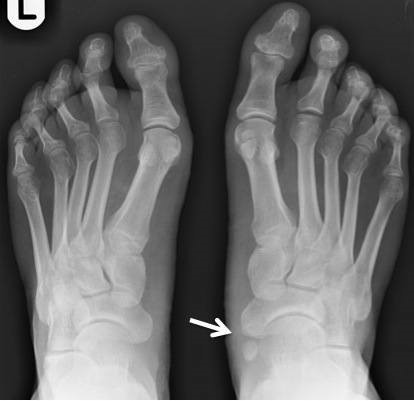

부주상골 증후군은 눈으로도 진단이 되기도 합니다. 발목 안쪽에 뼈가 튀어나와있습니다. 이 증후군은 스포츠 선수에게 많이 나타나는 발 손상입니다. 그리고 많은 분이 이 증상으로 군대를 면제받는지에 대해서 궁금해합니다.

이렇게 튀어나와 있는 뼈는 발 중간의 발등이나 아치에 위치한 작은 뼈 중 하나입니다. 나비 뼈라 불리며 여분의 뼈 중 하나이기도 합니다.

- 발 안쪽의 아치 바로 위 가시적 뼈 돌출